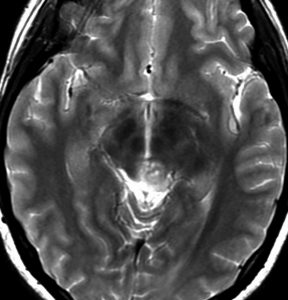

放射線化学療法後の画像です。腫瘍境界は不明瞭(左)で,腫瘍内出血(中央)して,左の視床に浸潤しています。かなりリスクは高いのですが,これを開頭手術で全摘出しました(右),この時点で完全寛解 CR です。この後にさらに化学療法と幹細胞移植(PBSCT,大量化学療法)が加えられました。